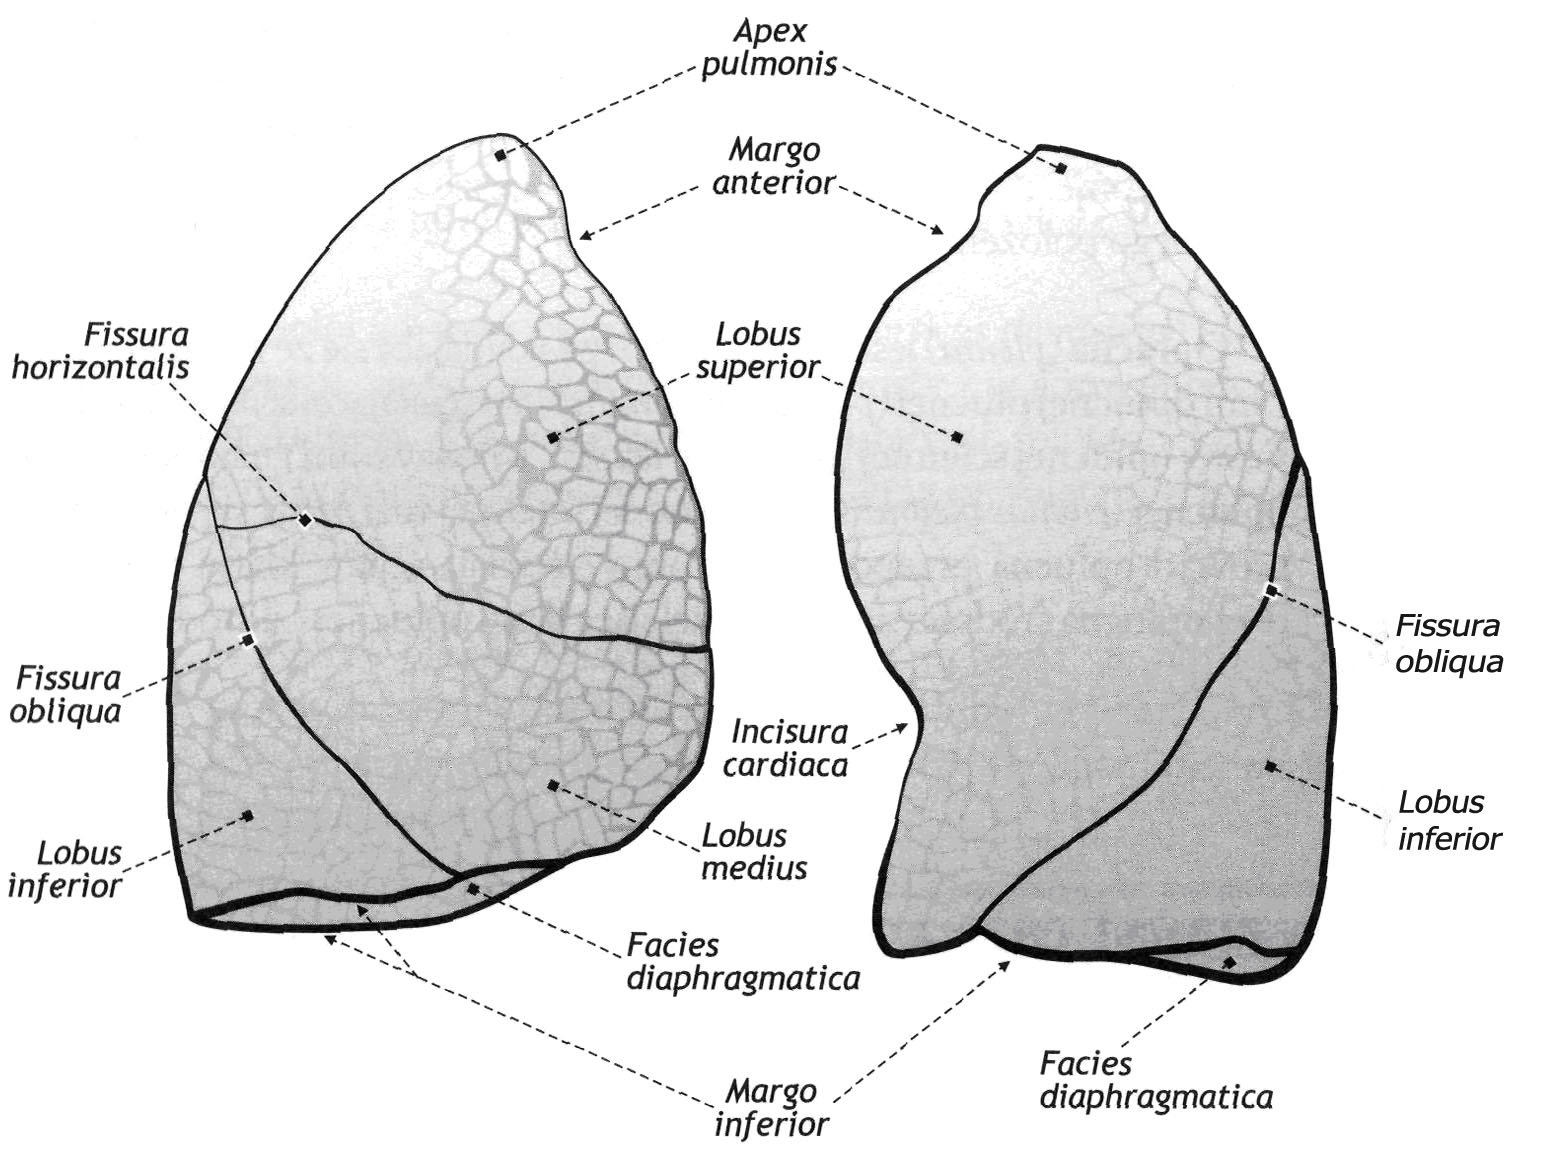

Анатомические изображения сегментов легких различных животных

Раздел: Другие животные